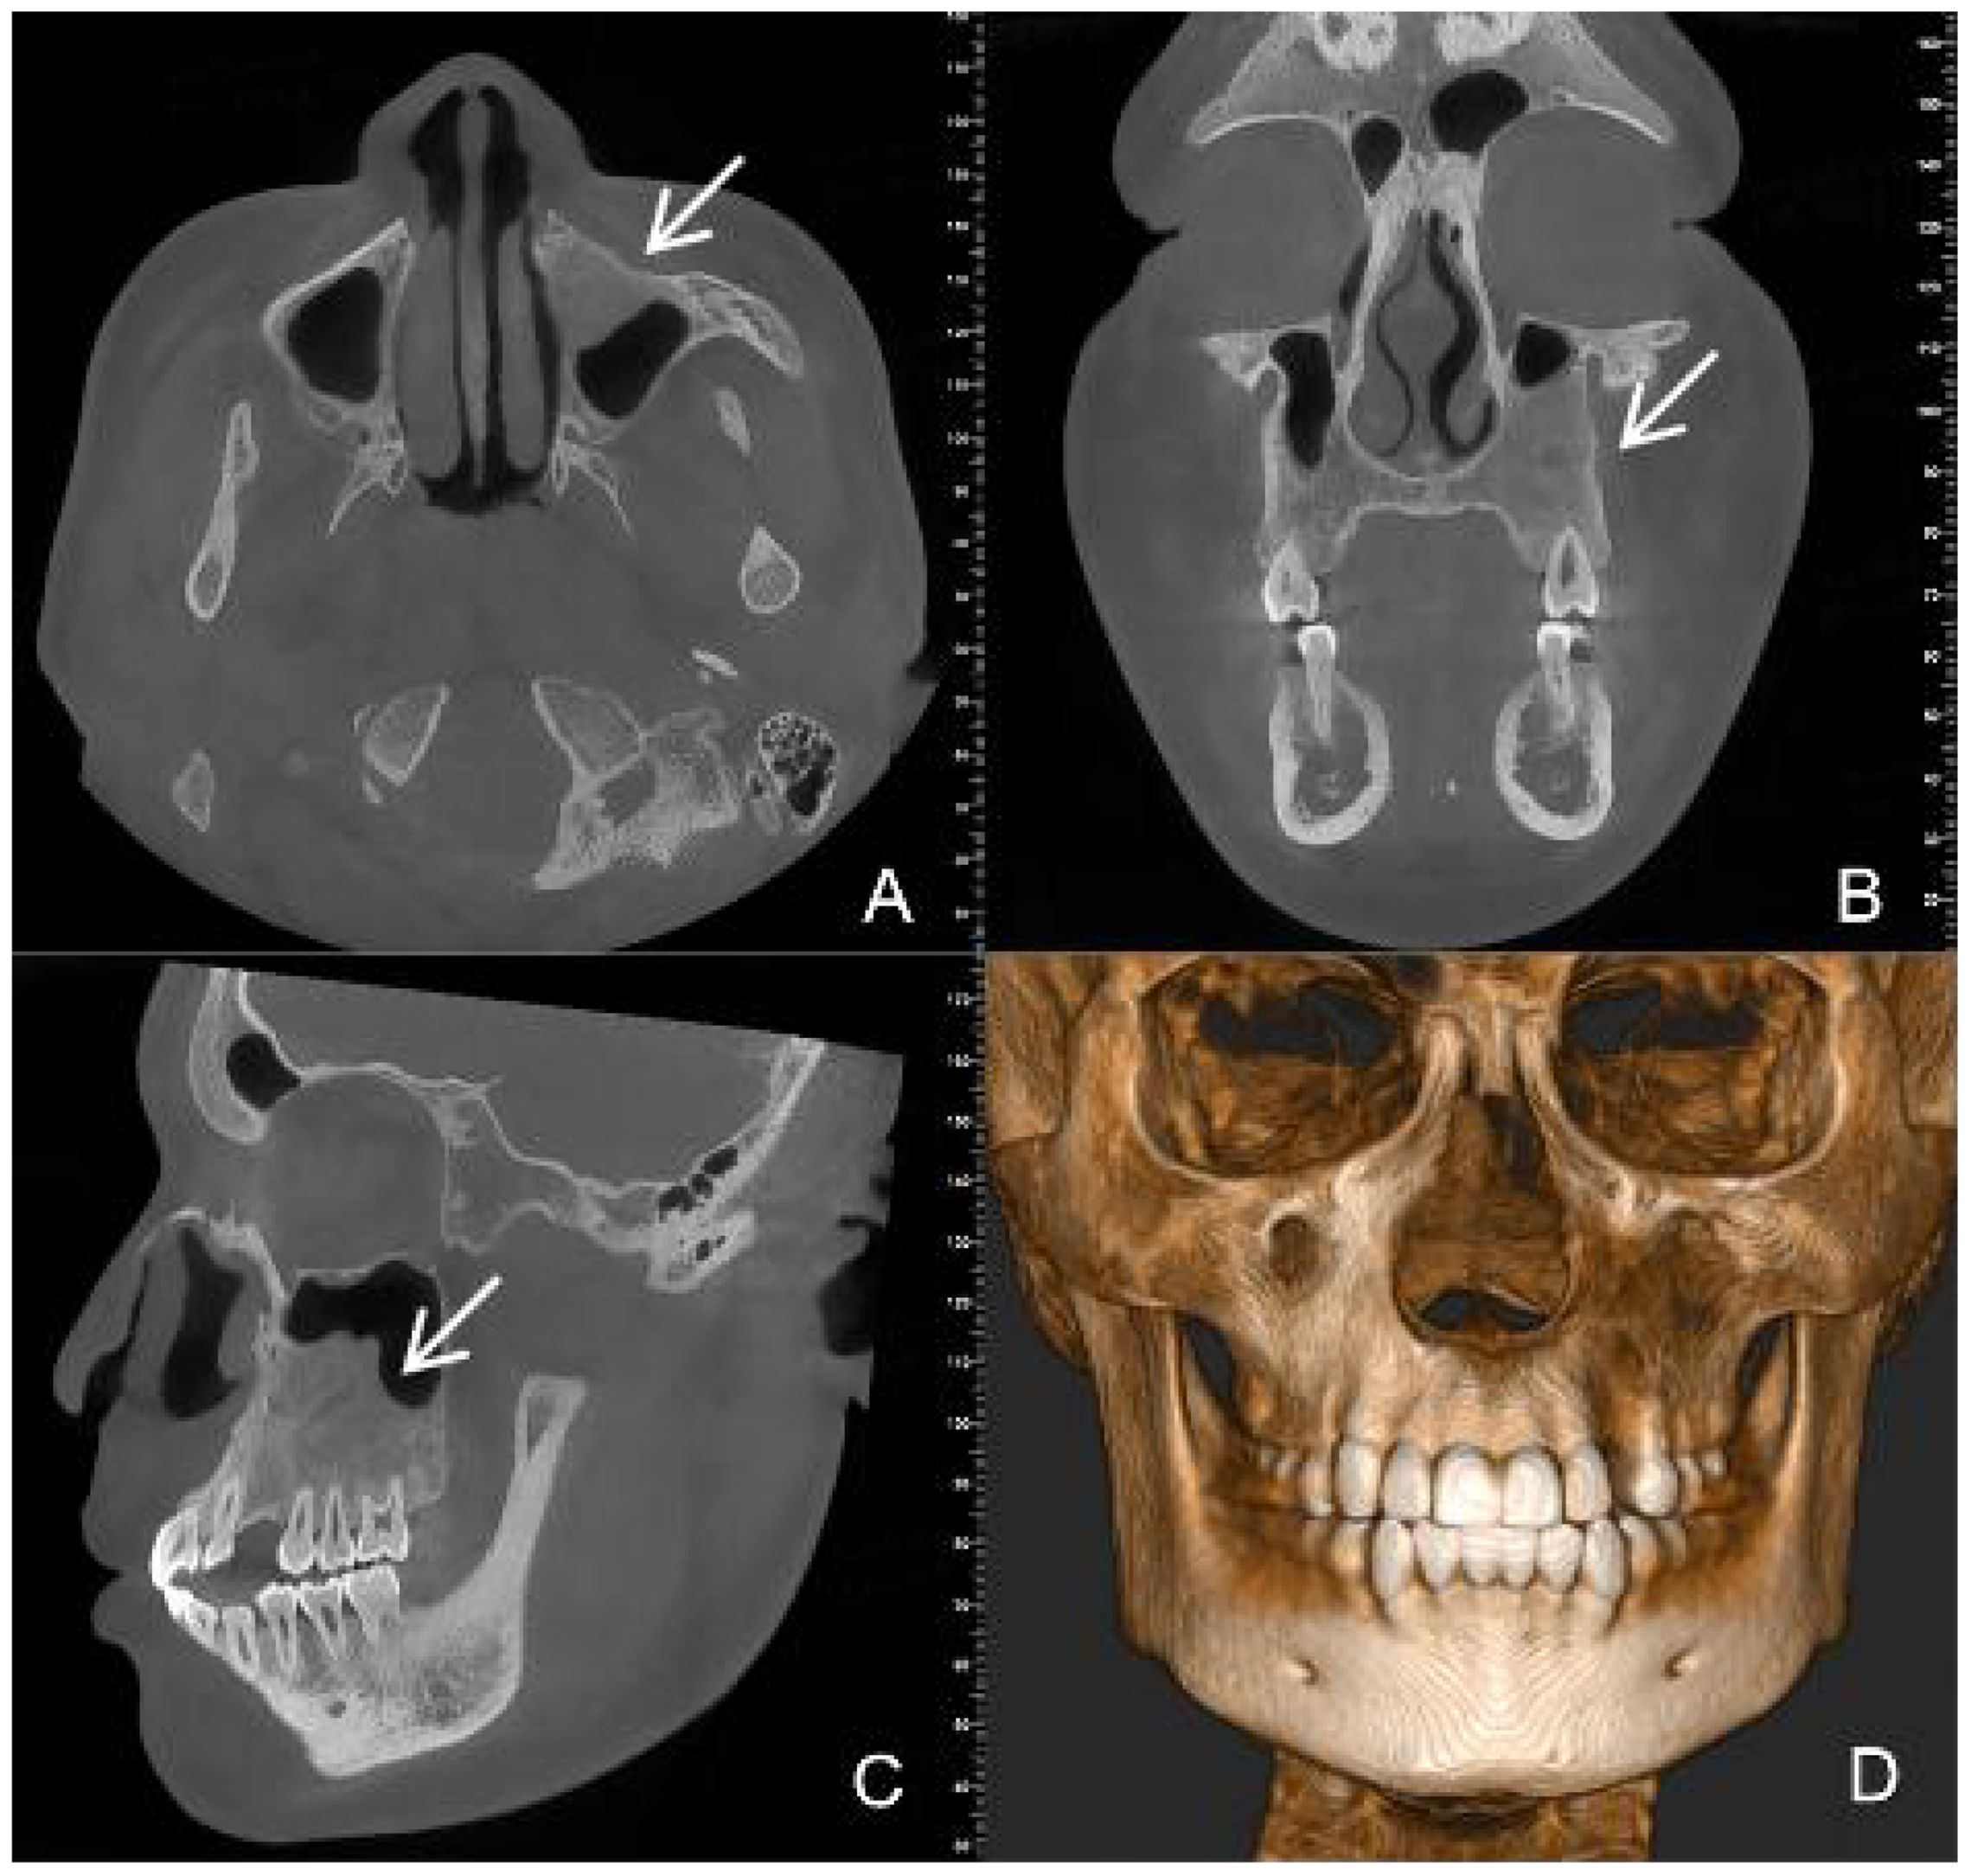

Dentinogenic ghost cell tumor (DGCT) is a rare odontogenic neoplasm that presents with nonspecific clinical manifestations and imaging features. It is more prevalent in elderly patients, with cases in children being extremely rare. This article presents a case study of a 10-year-old male patient who exhibited symptoms of swelling and pain in the left cheek for a duration of two weeks. Cone beam computed tomography (CBCT) demonstrated a hypodense lesion involving the left maxilla, with extension into the maxillary sinus and buccal cortical expansion. The patient underwent decompression, and histopathological examination of the intraoperative specimen suggested a diagnosis of calcifying odontogenic cyst (COC). One year after decompression, the patient underwent a tumor resection and the diagnosis of DGCT was confirmed by the post-operative pathology. Six months after tumor resection, CBCT showed complete bone remodelling in the lesion area. The patient is currently undergoing regular follow-up. This case provides an important reference for the diagnosis and treatment of pediatric DGCT, helping clinicians to develop individualised treatment plans.